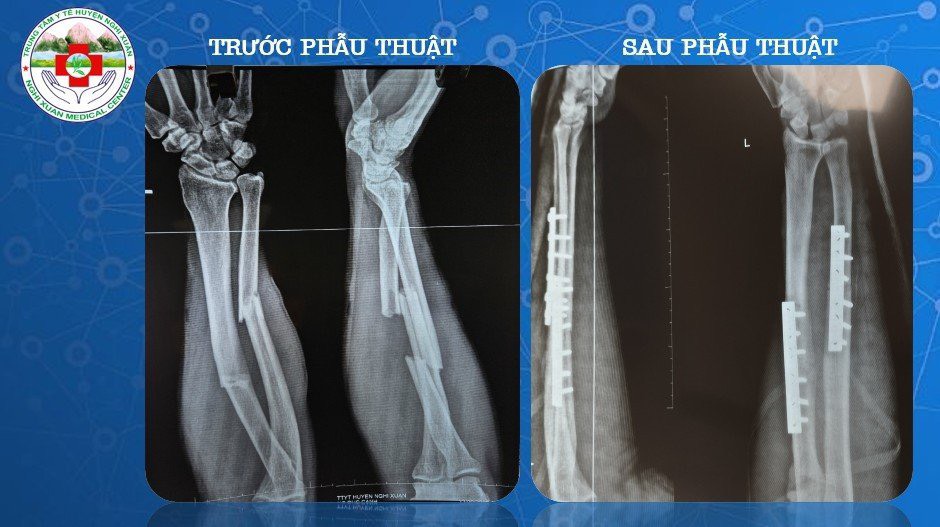

Qua thăm khám lâm sàng kết hợp với các phương pháp chẩn đoán hình ảnh, bệnh nhân được chẩn đoán: Gãy phức tạp 1/3 giữa 2 xương cẳng tay trái di lệch/ Gãy xương sườn. Các bác sĩ khoa Ngoại Tổng hợp đã nhanh chóng cấp cứu tích cực cho bệnh nhân cũng như hồi sức dự phòng chống sốc chấn thương, tiêm truyền thuốc giảm đau, hội chẩn và hoàn thiện xét nghiệm để tiến hành phẫu thuật kết hợp xương bệnh nhân một cách nhanh nhất. Sau 1 tiếng, ê kíp gây mê cùng các bác sĩ, phẫu thuật viên đã phẫu thuật thành công cho bệnh nhân. Hiện sức khỏe của bệnh nhân đã ổn định và được xuất viện.

Hình ảnh xương trước và sau phẫu thuật

Theo BS CKI Lê Viết Hùng – Giám đốc Bệnh viện- Nguyên Trưởng khoa Ngoại của Trung Tâm Y Tế cho biết: “Khoa Ngoại Tổng hợp hiện đang triển khai phương pháp phẫu thuật kết hợp xương bằng phương pháp sử dụng nẹp vít để cố định xương thẳng trục. Đây là phương pháp phòng ngừa biến chứng cho bệnh nhân gãy xương với nhiều ưu điểm như: Cố định vững chắc, bộc lộ chính xác vị trí ổ gãy xương, giảm số ngày nằm viện, điều kiện tập phục hồi chức năng sớm, bệnh nhân sớm trở lại sinh hoạt bình thường”. Được biết, các bác sĩ Khoa Ngoại Tổng hợp đã thực hiện rất nhiều ca phẫu thuật kết hợp xương hiệu quả bao gồm các phẫu thuật xương khớp như kết hợp xương trong gãy xương đòn, xương cánh tay, xương cẳng tay, xương đùi…Đó là tiền đề để các cán bộ, nhân viên y tế trong khoa không ngừng học tập nâng cao trình độ chuyên môn áp dụng vào trong công tác khám chữa bệnh cho nhân dân; giúp giảm tải cho tuyến trên và giảm chi phí điều trị cho bệnh nhân.